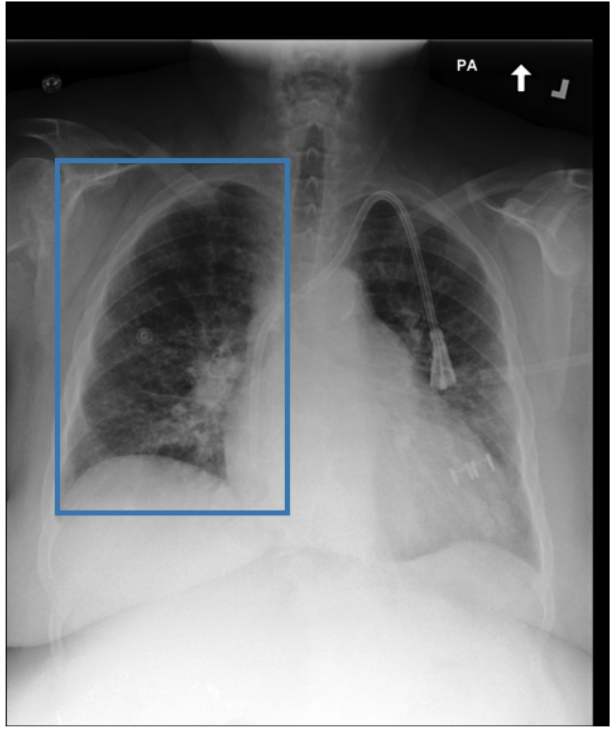

To address these drawbacks, state-of-the-art models such as MAIRA-2 [3] explicitly incorporate grounded report generation to better align local visual evidence with the textual findings. For example, MAIRA-2 is trained on a diverse set of localization-based tasks, including phrase grounding and grounded report generation. However, as shown in Figure 1, current models often exhibit a bias in which the target visual regions become overly associated with abnormal findings, leading to false positives in medical reports.

As shown in Table 1, our data composition reflects this imbalance: over 12.9M instances from Chest ImaGenome dominate the much smaller MS-CXR (815 PG instances) and PadChest-GR (12k instances) datasets. Beyond the imbalance between datasets, each dataset also exhibits substantial intra-dataset class imbalance. For example, anatomical regions in AGRG and semantic categories in PG are unevenly represented, leading the model to overfit frequent regions, neglect rare but clinically important ones, and hallucinate findings (Figure 1). Our curriculum framework addresses both sources of imbalance.

While MAIRA-2 exhibits a slightly lower hallucination rate for a few anatomies (e.g., ‘Cardiac Silhouette’), CURE consistently achieves a significantly lower contradiction rate and higher entailment rate across almost all categories. This improved performance likely stems from a key difference in the training data composition. Standard phrase grounding, used by MAIRA-2, is inherently biased towards abnormal findings. In contrast, our AGRG formulation exposes the model to both normal and abnormal descriptions for each anatomical region, leading to a more balanced and reliable generative process that mitigates the tendency to hallucinate abnormalities.